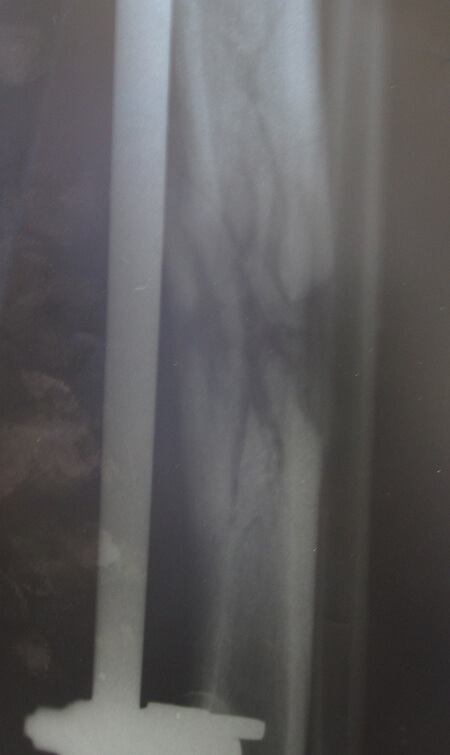

Figure 2a.

Figure 2b.

Figure 2c.

Figure 2a-c: Success story of patient treated by local surgeons: orthoplastic collaboration in country.

2a: 19-year-old male with a Gustilo IIIb middle 1/3rd tibia and fibular fracture, left leg

2b: Treated acutely with debridement and external fixator: x-ray at 2.5 months shows good alignment and signs of union.

2c: Fracture site was covered by a local fasciocutaneous flap within 11 days of the acute injury